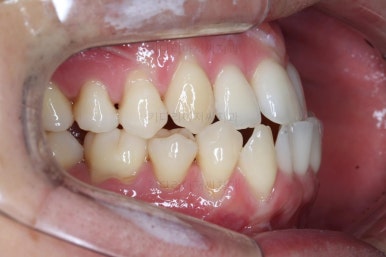

부산비수술교정 키다리아저씨치과에 처음 내원하셨을 당시의 입 안의 모습입니다.

아래 앞니에 결손치아가 하나 있네요. 송곳니-송곳니 사이에 앞니가 4개가 있어야 정상이지만 이 분은 3개에요. 의외로 아래앞니 하나 혹은 두개가 없는 경우가 굉장히 많답니다.

갯수가 맞지 않다보니 치열의 중앙도 맞지 않고 비대칭이 됩니다.

그리고 주걱턱이기 때문에 당연히 아랫니들도 앞으로 나올 수 밖에 없어 윗니보다 앞에 나와있어요.

이를 반대교합이라고 합니다.

어금니의 맞물림도 연쇄적으로 몇 칸씩 밀려있는 양상이라 효율도 좋지 못하고 치아의 건강에도 좋지 못해요.

이 분의 경우에도 전반적으로 잇몸이 약해져있을 수 밖에 없어요. 보시면 아시겠지만 잇몸 퇴축이 심해서 치아들이 길쭉길쭉해 보이죠.